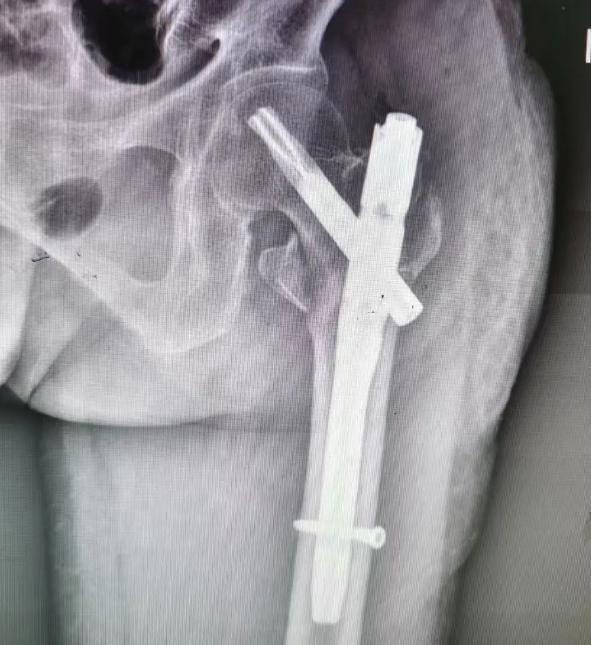

2月13日上午,在充分准备、评估各项风险并与患者家属再次深入沟通后,骨伤二科主任徐波及麻醉科和手术团队为喻奶奶实施了在腰麻下行“股骨骨折闭合复位髓内钉内固定术(右)”。

术中秉持解剖、微创、精准的理念,历经40分钟,手术顺利缝合结束,麻醉苏醒也十分顺利。

(▲术后伤口影像)